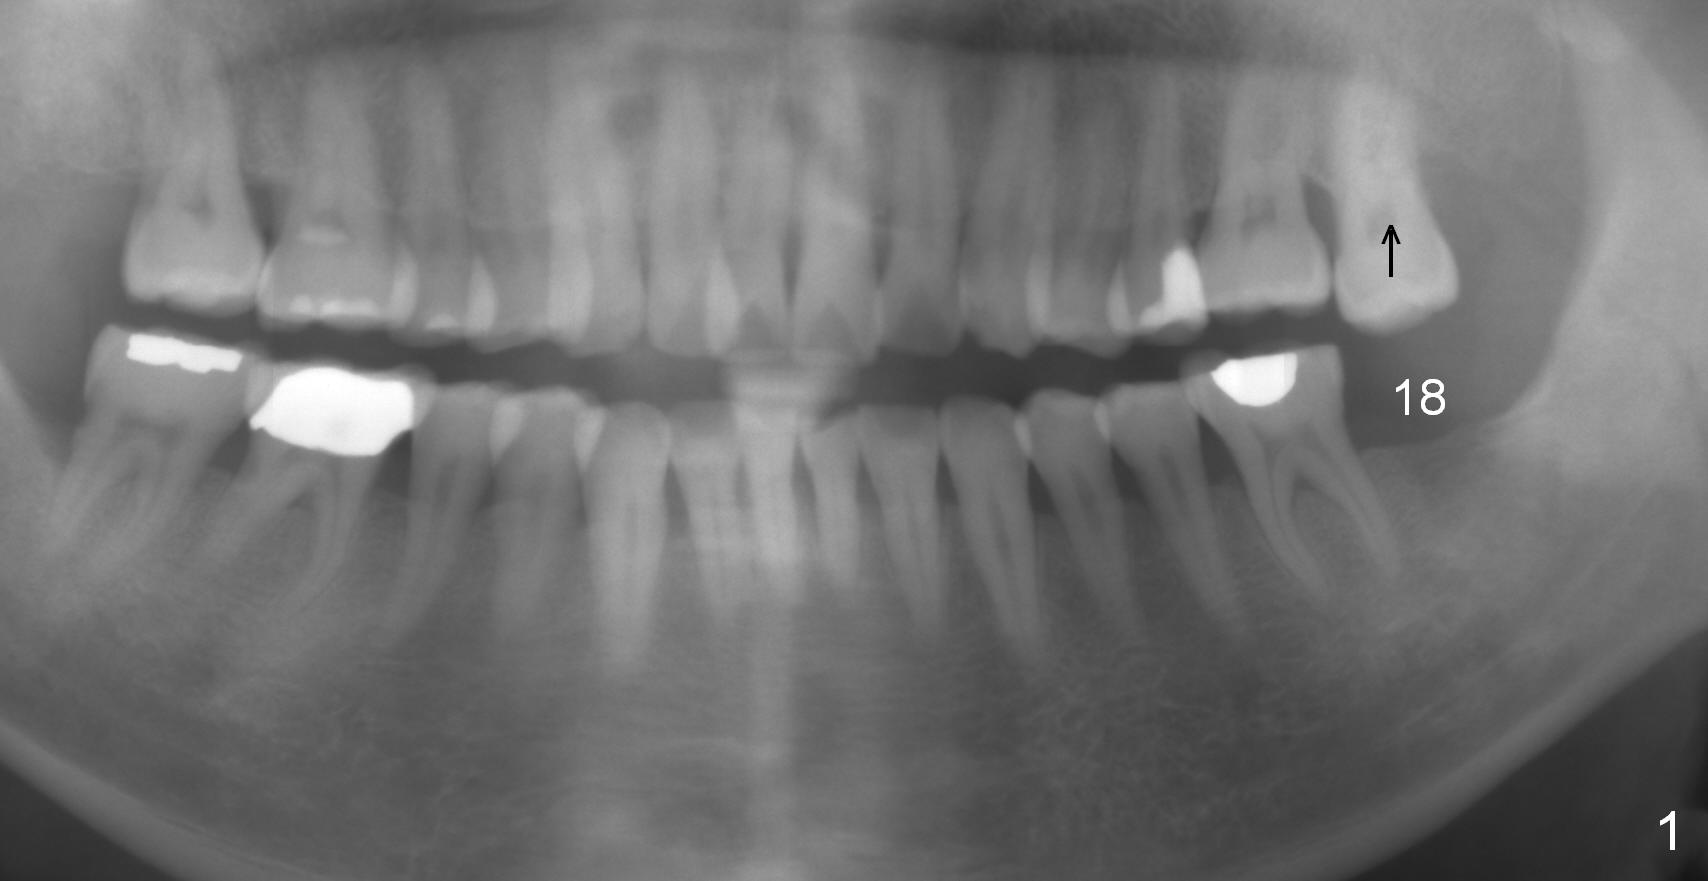

A 51-year-old man has lost #18 for more than 10 years (Fig.1,6). There appears to be sufficient bone height for implant (15 mm (Fig.7 (red dashed line: the superior border of the Inferior Alveolar Canal))). Prepare 4 mm implant spacer and SM starter drill and 2 mm pilot drill at 12 mm. Take PA. Palpation reveals that the edentulous ridge is wide. Place an implant in the middle of the ridge (buccolingually).

Next appointment, place 2 of mini-implants for #15 intrusion (Fig.1 arrow): one in MB (latch driver) and the other in DL (hand instrument).

In fact, the tooth 15 had basically no extrusion 6 years earlier (Fig.2) with even occlusal plane. When the tooth is intruded orthodontically, the occlusal plane may be not even (Fig.3). When the implant at #18 osteointegrates (Fig.4 green), fabricate a provisional (grey rectangle) with higher mesial occlusal surface. For certain period of time, the tooth #15 may change its axis so that the mesial portion of the tooth may be intruded more (Fig.5 arrow).

Four months post intrusion, the tooth #15 is distalized instead (Fig.9 arrow). To facilitate mesialization, the power chain is engaged into the mesiobuccal slot (Fig.10 <). It is 1 month after the change in position of the power chain. Has the tooth mesialized? Regional orthodontic devices are placed, but the patient is not cooperative, refusing any intrusion treatment. Prosthetic intrusion will be tried once the implant at #18 osteointegrates.